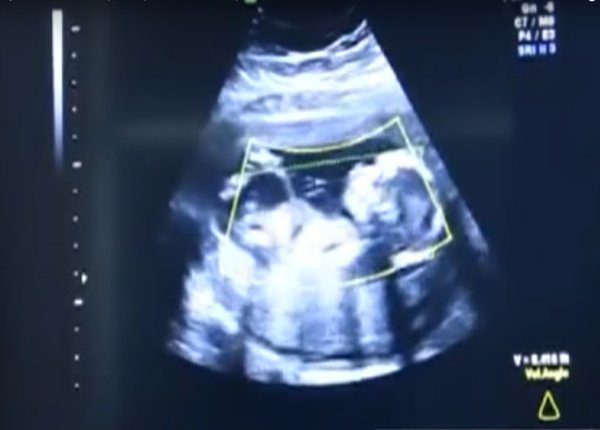

Az orvosok alaposan megvizsgálták a nőt, és alig hittek a szemüknek. A baba nem az anyaméhben, hanem a hasüregben volt – ezt nevezik méhen kívüli terhességnek, amikor a megtermékenyített petesejt a méh üregén kívül van. Az ilyen terhesség az anyát életveszélyes állapotba sodorhatja, és ha felmerül egy ilyen helyzet, akkor azonnali orvosi beavatkozásra van szükség.

Nagyon ritka az olyan esetek száma, ahol a csecsemő egészségesen kifejlődhet a méhen kívüli terhesség esetében. Ilyenkor az édesanyák csakis császármetszéssel hozhatják világra a gyermeküket.

Amikor az orvosok eltávolították a magzatburkot az édesanya hasüregéből, csodának lehettek szemtanúi. A kislány teljesen kifejlődött, lélegzett és súlya több mint 4 kg volt. A büszke édesanya úgy döntött, hogy lányának egy különleges nevet fog adni, ezért Veronikának nevezte, amelynek jelentése győzelmet hozó.